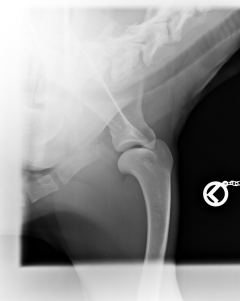

Bayou ist HD frei, ED frei und OCD frei.Beste Vorraussetzung für ein Deckrüde.

HD                                                           ED-Rechts                                         ED-Links                                                 OCD-rechts                                            OCD-links